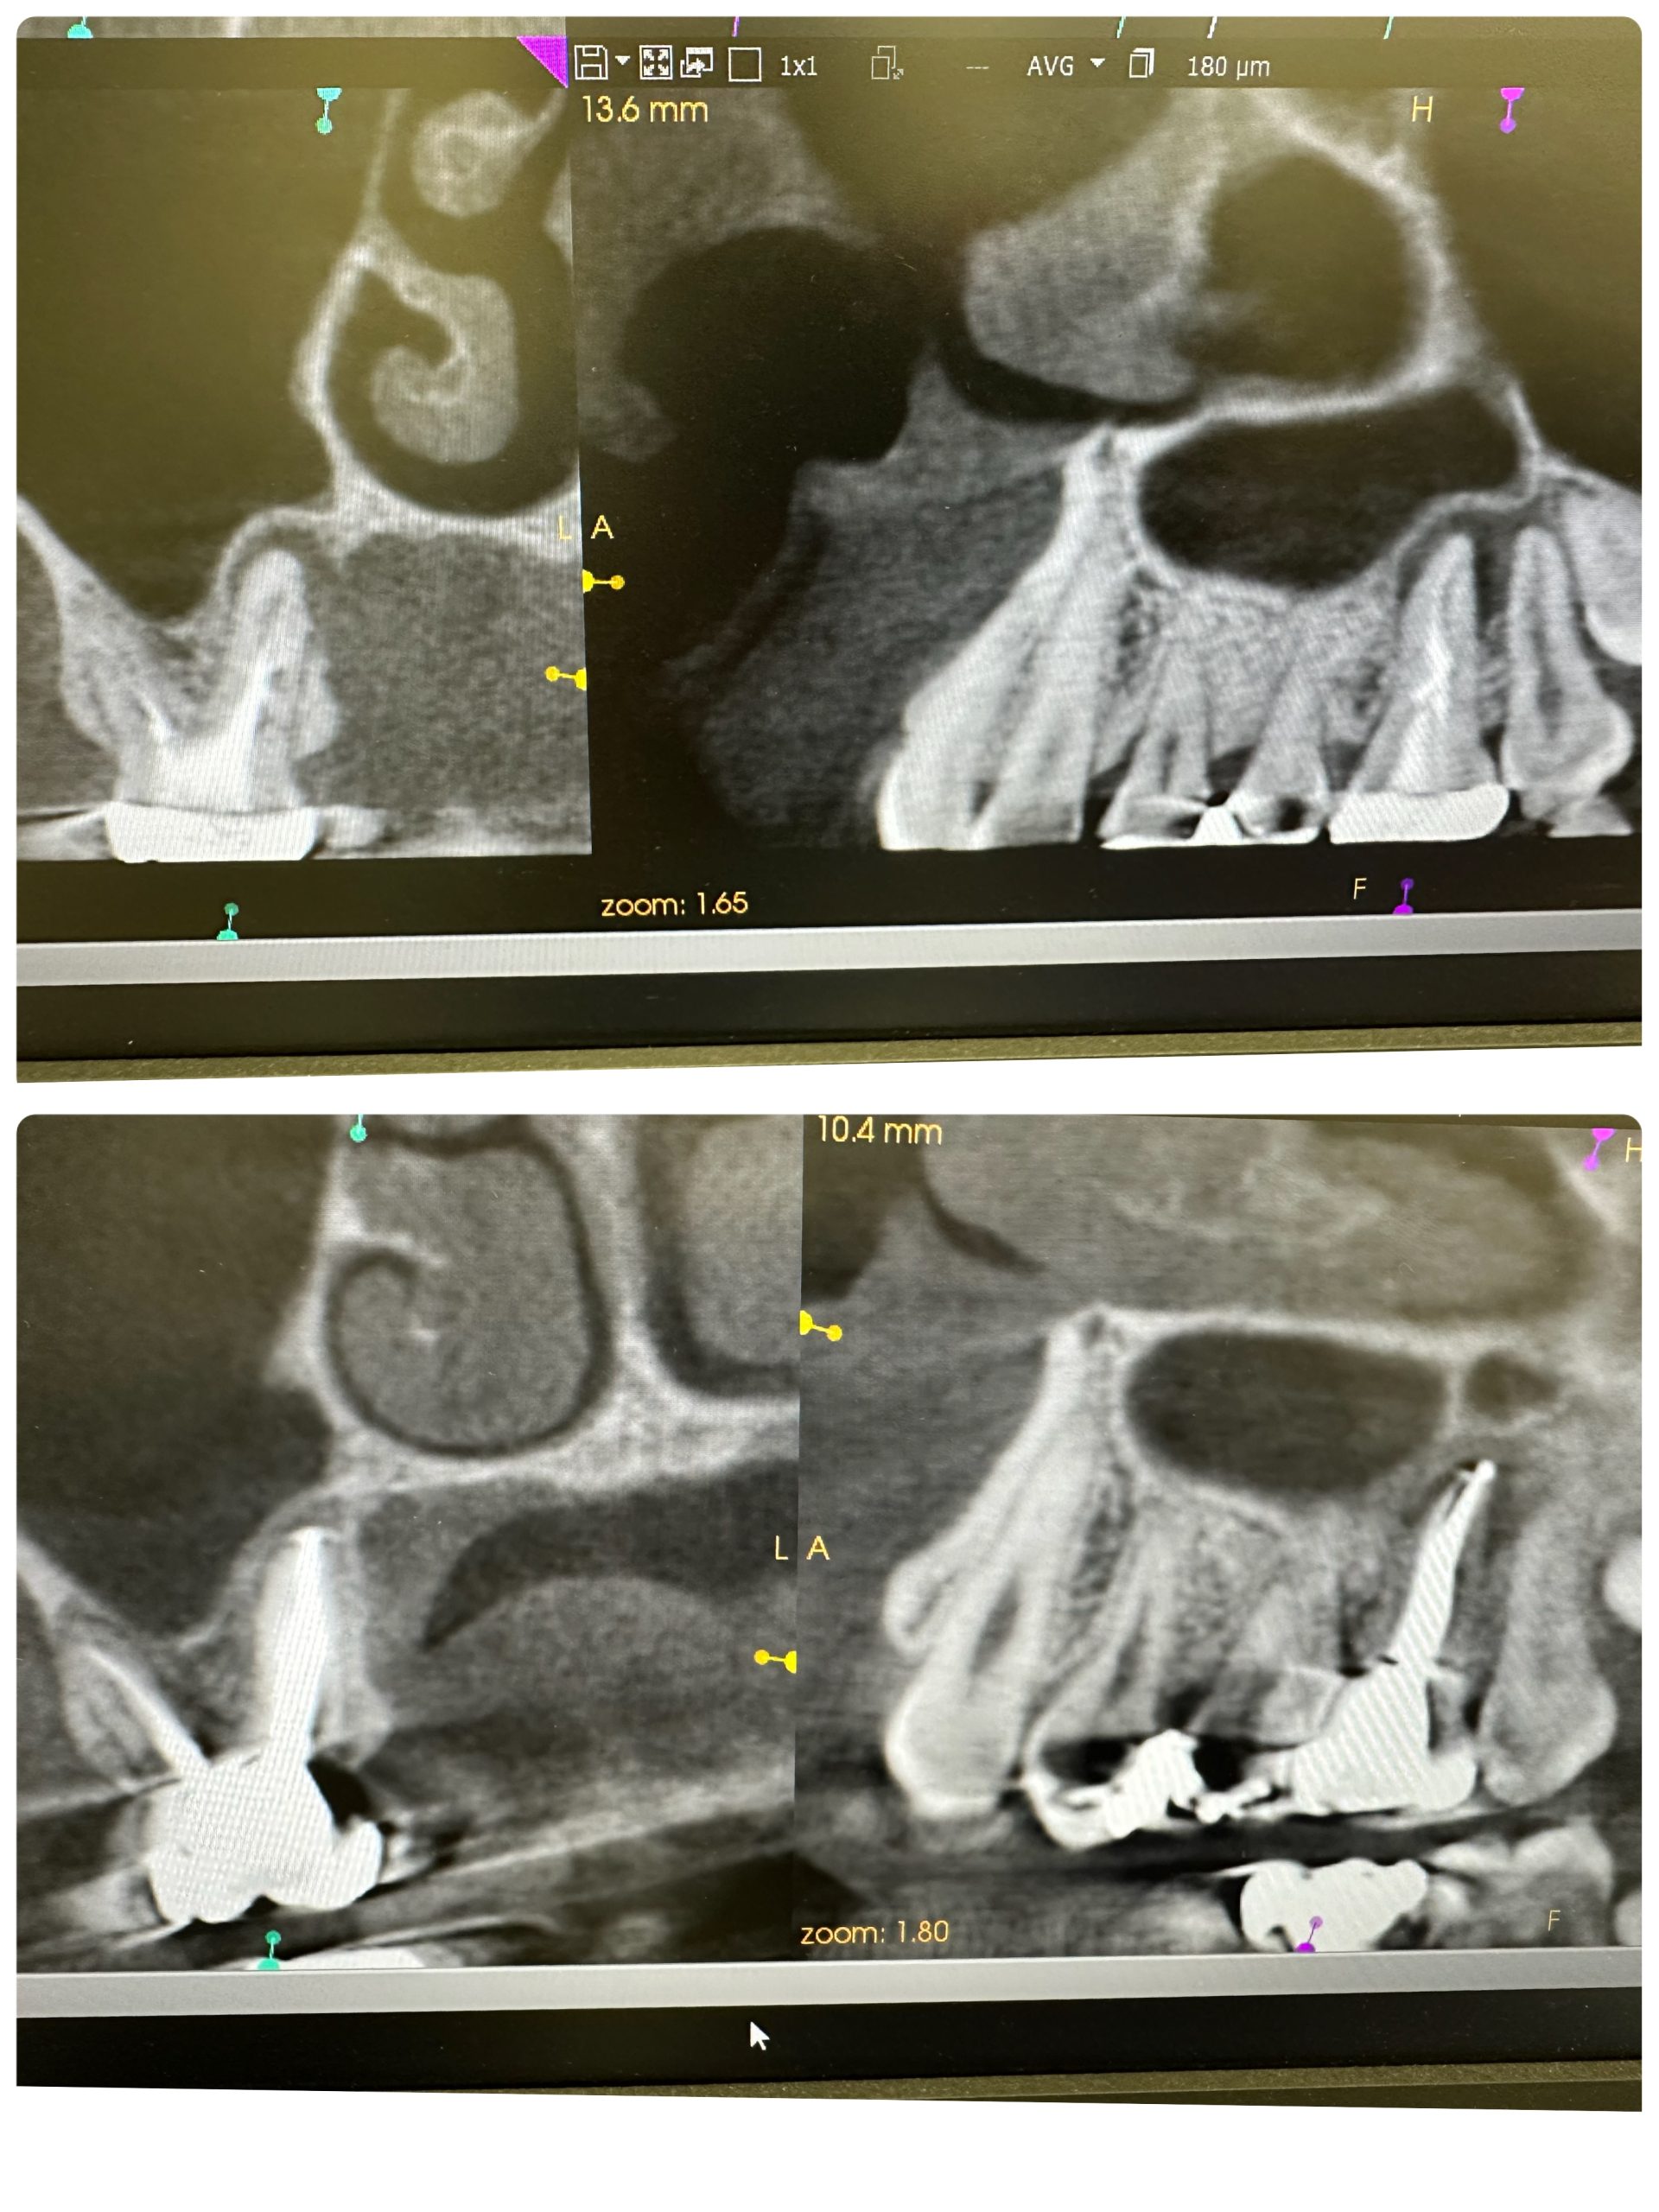

ネチネチ、チマチマ系の根管治療4本

パラタルプレートの再生、ヤグレーザー併用の根管治療のみ

経過みないとね、自然治癒力は素晴らしい!

外科処置の勇み足にならない為の良い症例

最小侵襲で治癒導くが重要

CT撮影は、算定要件満たしてない為に無料😭

咀嚼に耐え得る歯は保存!